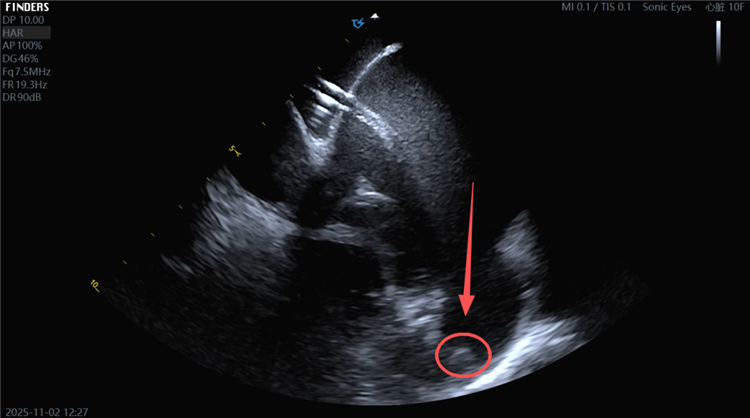

超声提示患者左心耳内血栓形成。

左心耳血栓。

手术在局部麻醉下进行。团队在DSA及ICE引导下精准穿刺房间隔,清晰观察到左心耳内10mm×6mm的血栓。术中,团队评估左心耳形态与大小,选定合适的封堵器,顺利完成封堵操作。经多角度评估,封堵器位置形态良好,符合PASS原则,牵拉试验及多普勒扫描显示封堵完全,无残余分流,手术成功。